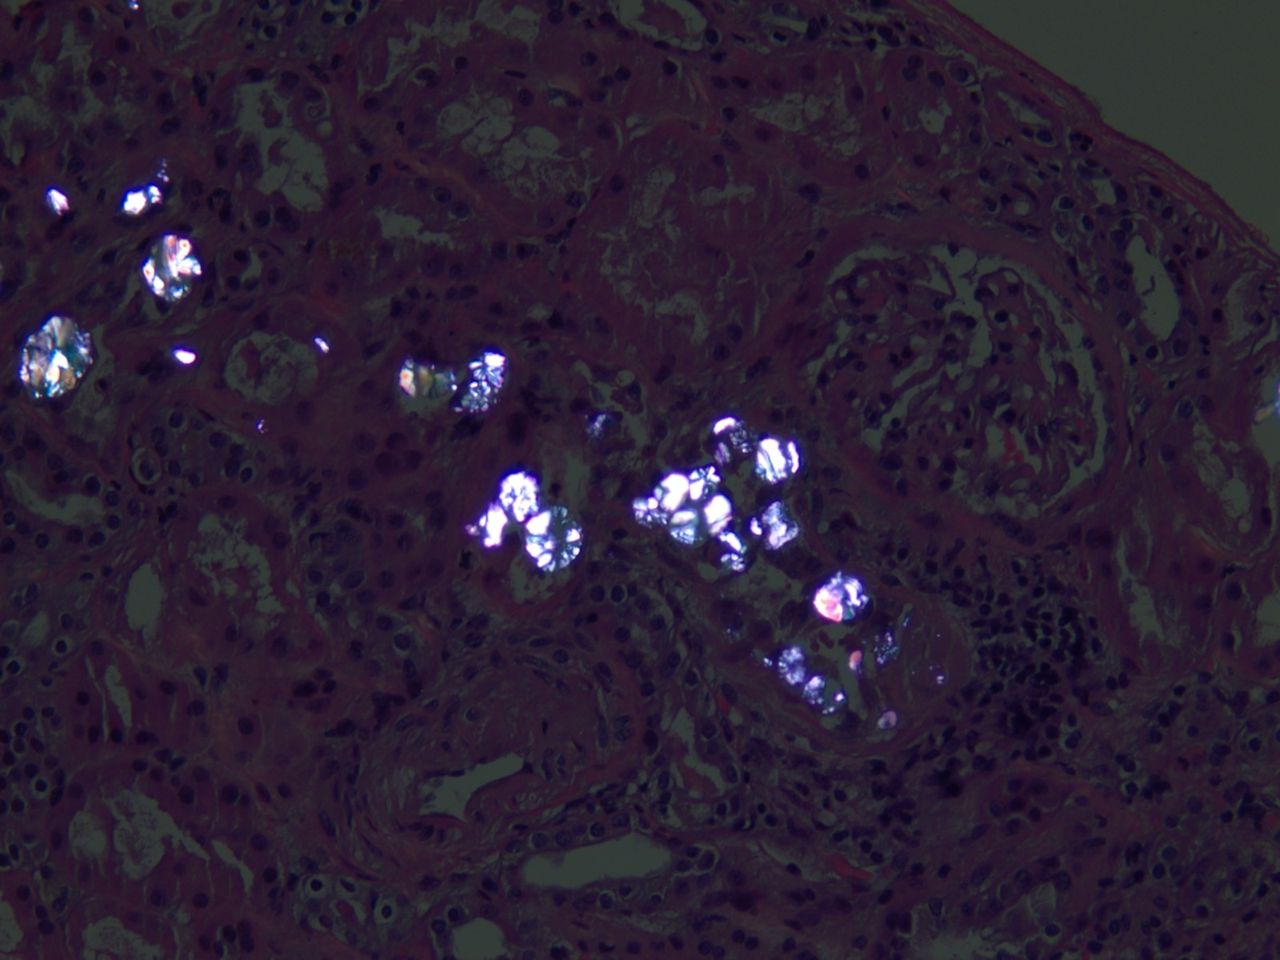

Фото Оксалата Милого

Фото Оксалата Милого 114 фото